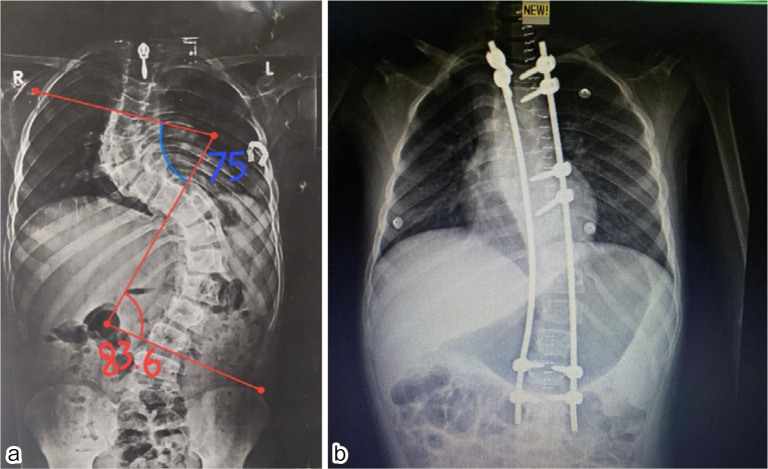

Background: Distraction-founded techniques such as traditionally growing rods or magnetically controlled growing rods are the almost globally accepted management patterns for early onset scoliosis. However, periodic lengthening operations are still needed. Moreover, an MCGR is difficult to contour, and implant-associated problems are common. We developed concave side apical control of the growing rod in which an additional anchor site is inserted at the apex to enhance stability and assist in the adjustment of axial deformity.

Results: In this study, 15 patients were involved. The mean age was 7 years. The mean preoperative Cobb angle was 48°, which postoperatively became 12° with the percentage of coronal correction reaching 75.73%. The mean Cobb angle degrees of correction were 39°. T1-S1 height increased by 10 mm/year. Postoperative complications occurred in two cases with single rod technique and rod breakage.

Conclusions: The concave side apical control of the growing rod seems to be a hopeful surgical procedure for the management of EOS. Curve correctability in patients was 60% and can be sustained for a minimum of 2 years. Reoperations and complications might not be constricted, but the complication frequency looks more reasonable than in the current systems.